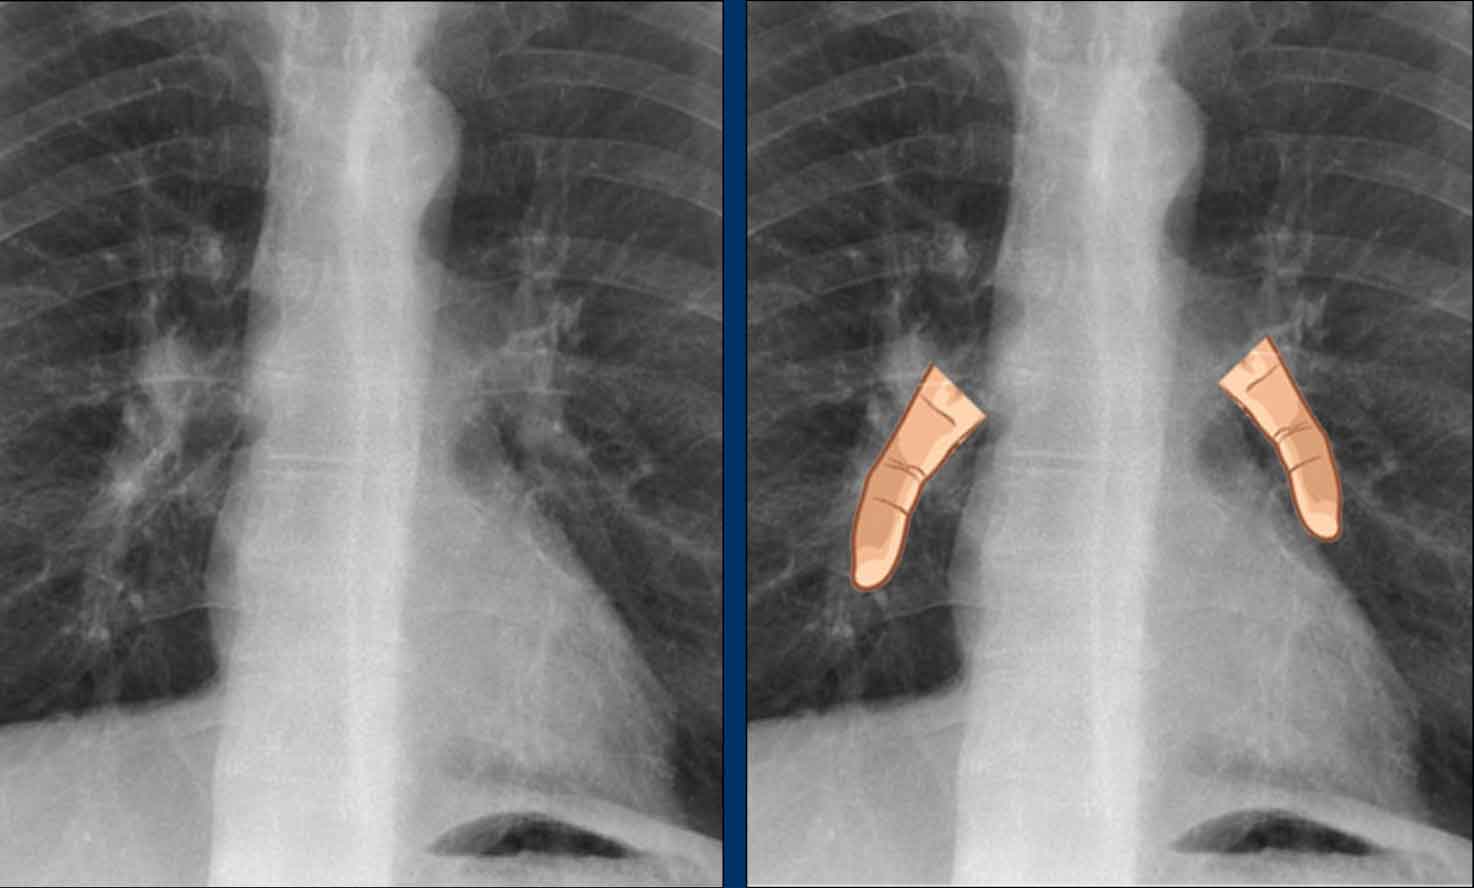

Pericardial calcifications associated with constrictive pericarditis. Pericardial calcifications associated with constrictive pericarditis.

Cardiac and Pericardial Calcifications

• Coronary artery calcifications (indicative of atherosclerosis).

• Valvular calcifications (commonly involving the aortic and mitral valves).

• Pericardial Calcification are less common and may indicate chronic pericardial disease, particularly constrictive pericarditis. Appears as linear or curvilinear calcifications along the pericardial contour.

Here we see pericardial calcifications which can be associated with constrictive pericarditis.

Myocardial Calcification vs. Pericardial Calcification:

• Myocardial infarction-related calcification can resemble pericardial calcification.

• Distinction: Myocardial calcifications follow the contour of the left ventricle and are located within the myocardium, not along the pericardium.

In this case there are calcifications that look like pericardial calcifications on the chest X-ray, but these are myocardial calcifications in an infarcted area of the left ventricle.

Notice that they follow the contour of the left ventricle.